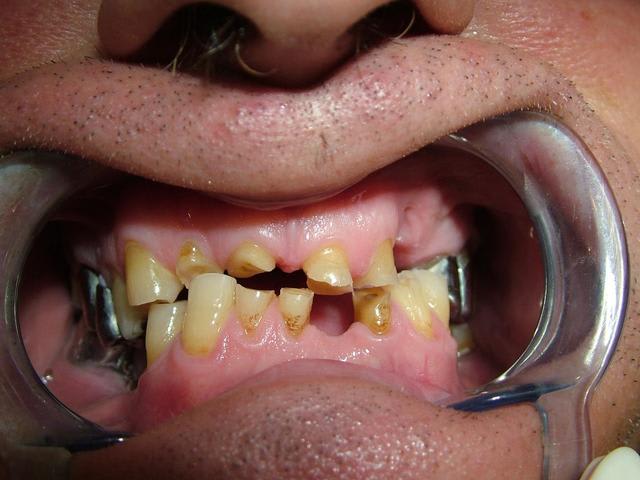

Ma première idée de dire que l'occlusion était faussée par des contacts prématurés,des déviations des egressions,et qu'il fallait en premier lieu essayer de la retrouver dans une position plus conforme à la normale

L'usure des dents antérieures en est peut-être le résultat

Solène, voici un cas semblable au tien, les images parlent plus qu'un long discours, j'ai commencé la surélévation en réalignant au maximum les milieux (freins incisifs) et en confiant à mon patient un Soulet-Besombes pour classe III, pour l'instant malgré quelques difficultés pour manger, il se trouve bien dans sa nouvelle occlusion, la suite en septembre.

Tout d'abord les photos avant traitement

on peut pas augmenter la dv comme ca sans repere le patient aura une sensation de bouche pleine. au debut g cru que la mise sur articulateur été fausse apres avce les image de bouche du patient bfff il y a un contact posterieur il y a pas d'abrasion en principe la dvo est conservée mais le plan d'occlusion est tres perturbé. au niveau posterieur ou on peut observer des egressions mais surtout au niveau anterieur je me demande meme s'il y a pas un defaut des bases osseuses.